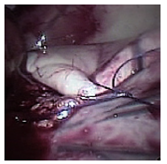

Our results support the rabbit as a suitable animal model for the teaching and practice of Nissen fundoplication by laparoscopy. However, it might not be appropriate for human surgeons to develop the more complex skills required to master the technique, due to anatomical differences between both species (Table 2). In effect, for early learning stages, the rabbit was an excellent model in which to perform knots and the periesophageal wrapping cuff using laparoscopic instruments (Figs. 3 -7). Formation of knots is one of the most difficult elements of the technique in human surgery. Consequently, preliminary training with simulators is recommended.1,3 Indeed, ligation of gastric short vessels is considered to be the most difficult maneuver of this surgery.33 In addition, ligation of the short vessels is essential for fundoplication because it can decrease morbidity of patients undergoing laparoscopic surgery.34 However, it is worth mentioning that there is a Nissen-Rossetti procedure in which ligation of the short gastric vessels is not necessary.6 Moreover, an easier and faster Nissen fundoplication technique allows to avoid the cutting of the short gastric vessels altogether.35